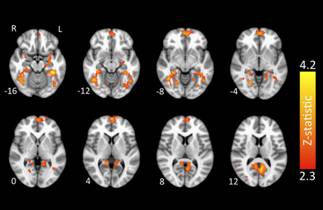

运动作为一种丰富的环境刺激对大脑发育和成熟以及延缓衰老有着重要的影响,对其神经机制的解答对于“脑老化”病症具有重要的现实意义。但迄今为止,现有的主要研究目标还多集中在小肌肉群的活动引起的大脑功能的变化上,人们还无法明确地回答基本的运动技能学习到底对大脑产生了何种程度的影响。基于此,该研究突破了传统的在扫描设备中进行真实动作的实验设计思路,利用表象动作与真实动作的“功能等价”理论,引入表象任务,将运动专家与新手进行同任务的对照研究,分析了运动技能获得所引起的大脑功能性变化,结果发现:(1)运动专家知识系统具有特殊的神经表征,该表征形式与技能特点密切相关;(2)只有专家在表象动作时会显著激活PFC,提示PFC可能参与了运动专家动觉表象的调控。本研究结果支持了假设,即认为经过多年训练的运动专家表现出与经验有关的优化网络模式。

图1 专业动作表象的组间激活差异